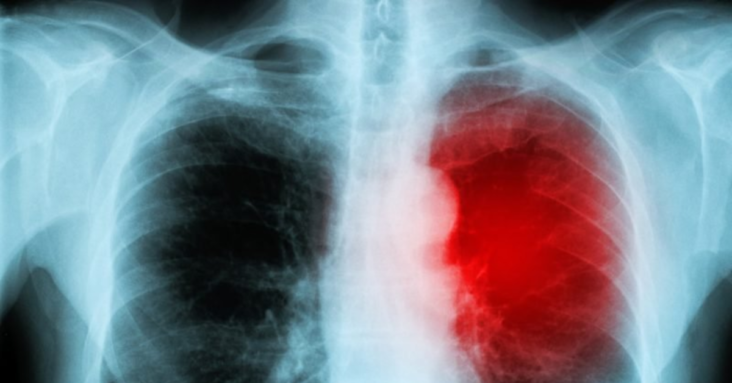

“Although vaccine-induced myocarditis is not often fatal in young adults, MRI scans reveal that, of the ones admitted to hospital, approximately 80% have some degree of myocardial damage. It is like suffering a small heart attack and sustaining some – likely permanent – heart muscle injury. It is uncertain how this will play out in the longer-term, including if, and to what degree, it will increase the risk of poor quality of life or potentially more serious heart rhythm disturbances in the future.”

An analysis of relative myocarditis risk by Oxford researchers who published a paper in Nature Medicine on December 14th. The authors find higher rates of vaccine-induced myocarditis than myocarditis from infection in males ages 16 – 39 across multiple vaccine doses: Pfizer dose 2 & 3 and Moderna dose 1 & 2.

A study from Israel found that males aged 16 to 29 faced the greatest risk, with around 11 in 100,000 males developing post-vaccination myocarditis. A pre-print study last year comparing risks of infection versus vaccination found that boys aged 12 to 15 were four to six times more likely to develop myocarditis from the vaccine than become hospitalized with any Covid-related condition

Incidence of myocarditis rocketed from spring 2021 when vaccines were rolled out to the younger cohorts having remained within normal levels for the full year prior, despite COVID-19 with the most up-to-date evidence. The paper from Israel found that the infection itself, prior to roll-out of the vaccine, conferred no increase in the risks of either myocarditis or pericarditis from COVID-19.